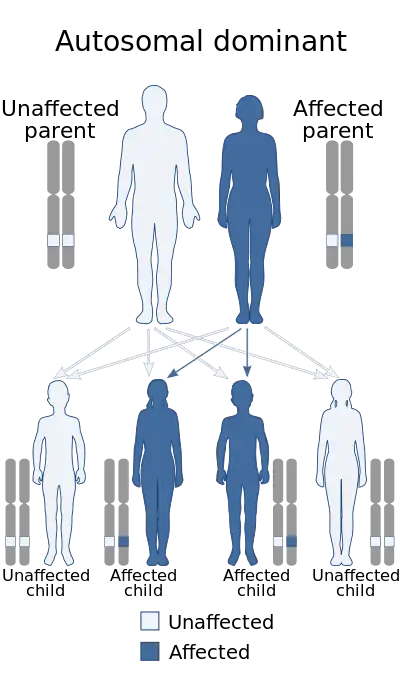

Adult osteopetrosis

Autosomal dominant osteopetrosis (ADO) is also known as Albers-Schonberg disease. Most do not know they have this disorder because most individuals do not show any symptoms. However, the ones that do show symptoms will typically have a curvature of the spine (scoliosis), and multiple bone fractures. There are two types of adult osteopetrosis based on the basis of radiographic, biochemical, and clinical features.

The various types of osteopetrosis are caused by genetic changes (mutations) in one of at least ten genes. There is nothing a parent can do before, during or after a pregnancy to cause osteopetrosis in a child.[4]

- Mutations in the CLCN7 gene cause most cases of autosomal dominant osteopetrosis, 10-15% of cases of autosomal recessive osteopetrosis (the most severe form), and all known cases of intermediate autosomal osteopetrosis.

Mutations in at least nine genes cause the various types of osteopetrosis. Mutations in the CLCN7 gene are responsible for about 75 percent of cases of autosomal dominant osteopetrosis, 10 to 15 percent of cases of autosomal recessive osteopetrosis, and all known cases of intermediate autosomal osteopetrosis. TCIRG1 gene mutations cause about 50 percent of cases of autosomal recessive osteopetrosis. Mutations in other genes are less common causes of autosomal dominant and autosomal recessive forms of the disorder. The X-linked type of osteopetrosis, OL-EDA-ID, results from mutations in the IKBKG gene. In about 30 percent of all cases of osteopetrosis, the cause of the condition is unknown.[14]